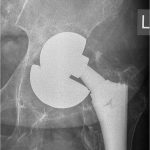

Πρόκειται για επεμβάσεις αναθεώρησης/revision των αρθροπλαστικών με τις οποίες γίνεται αφαίρεση μέρους ή όλων των αρχικών προθέσεων και αντικατάσταση με καινούργιες προθέσεις.

Κάθε περίπτωση έχει ιδιαιτερότητες που σχετίζονται με το είδος της αρθροπλαστικής που πρέπει να αναθεωρηθεί, με τον τρόπο που θα αφαιρεθούν οι παλιές προθέσεις, με την τεχνική κάλυψης των οστικών ελλειμάτων που συνήθως υπάρχουν στην περιοχή, με τον τρόπο που πρέπει να στερεωθούν τα καινούργια υλικά, με τον χειρισμό των μαλακών μορίων κ.α.

Στις περισσότερες περιπτώσεις η επέμβαση αναθεώρησης των αρθροπλαστικών δεν έχει καμία σχέση με τις τεχνικές και τα υλικά που χρησιμοποιούνται στις αρχικές αρθροπλαστικές.